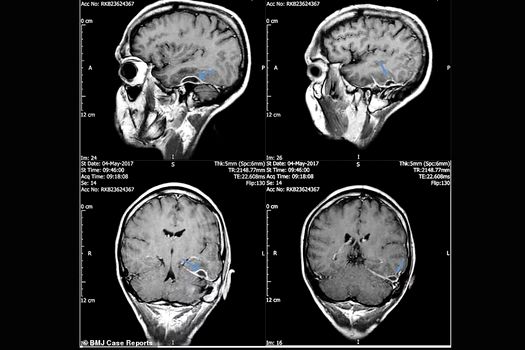

În tomografiile folosite pentru a-l diagnostica, s-au putut vedea „mici spaţii goale” între creier şi os. Medicii i-au curăţat urechea şi i-au administrat antibiotice intravenos, iar după 10 săptămâni bărbatul s-a recuperat complet.